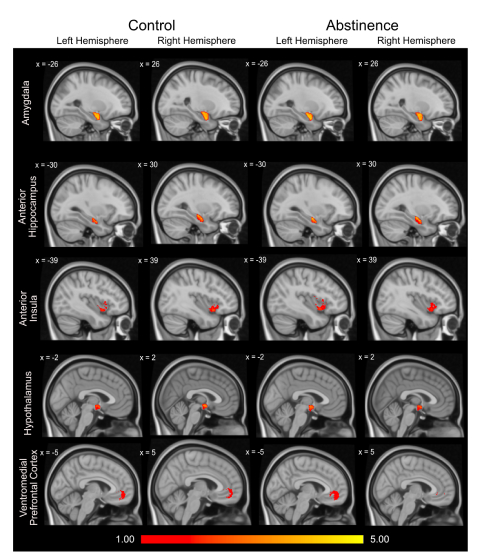

A novel neuroimaging study provides the first evidence that a small region of the brain, called the bed nucleus of the stria terminalis, has gender-based network structural connectivity differences in early abstinence from alcohol. Through the brain-imaging technique Diffusion Tensor Imaging, the researchers used 3D modeling to identify the structural nerve tract connections of the BNST, which regulates stress responses and anxiety-like behaviors during abstinence from alcohol. This is the first time that BNST structural networks in early abstinence have been studied in humans.

The key finding was that women in the abstinence group showed stronger overall BNST network structural connectivity compared with women in the control group, a difference that was not seen in men. Women also showed differences compared with men in the strength of BNST structural connections to two specific brain regions. These results expand on previous findings of sex differences of the BNST in alcohol use disorder and in abstinence—including that women are more likely than men to relapse as result of anxiety symptoms.

Women in early abstinence from alcohol use disorder show important alterations in brain connectivity that could underlie anxiety-induced relapse. Long-term recovery from AUD is challenging, particularly through periods of stress or uncertainty. In the early abstinence phase, the anxiety symptoms can be temporarily relieved by alcohol, creating a powerful motivation to resume drinking. Thus, understanding the neural changes of abstinence-related anxiety is critical for understanding, and ultimately preventing, AUD relapse.